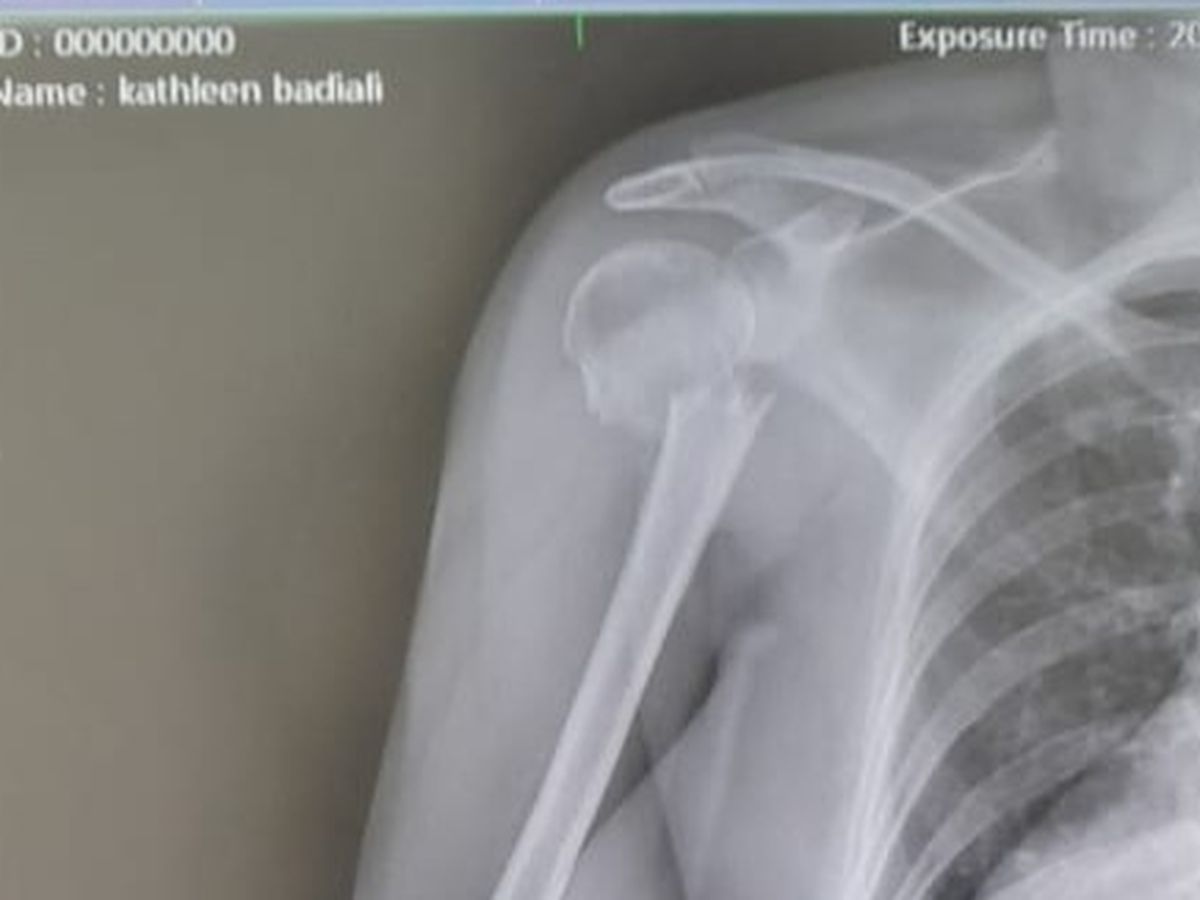

Last week I left for a 3-week trip to the US and she agreed to house/pet sit for me. A few days in, she slipped on a wet tile in my house and badly broke her right arm. With the help of several friends, we were able to get her to the hospital but upon arrival, they told her that they couldn't do surgery if she didn't have the cash to pay up front (they need ~$10K for the surgery alone).

Because she's not a CR resident, she can't be treated in the public hospital. She doesn't have travel or international health insurance to cover a private hospital. And because she's so badly injured, it's not safe for her to fly back to the US to have the surgery, and most likely the airlines wouldn't let her fly in her condition anyway.

She is in desperate need of our help. She's in excruciating pain and needs this surgery ASAP not only to relieve the pain but to give her the best chance at a complete recovery.